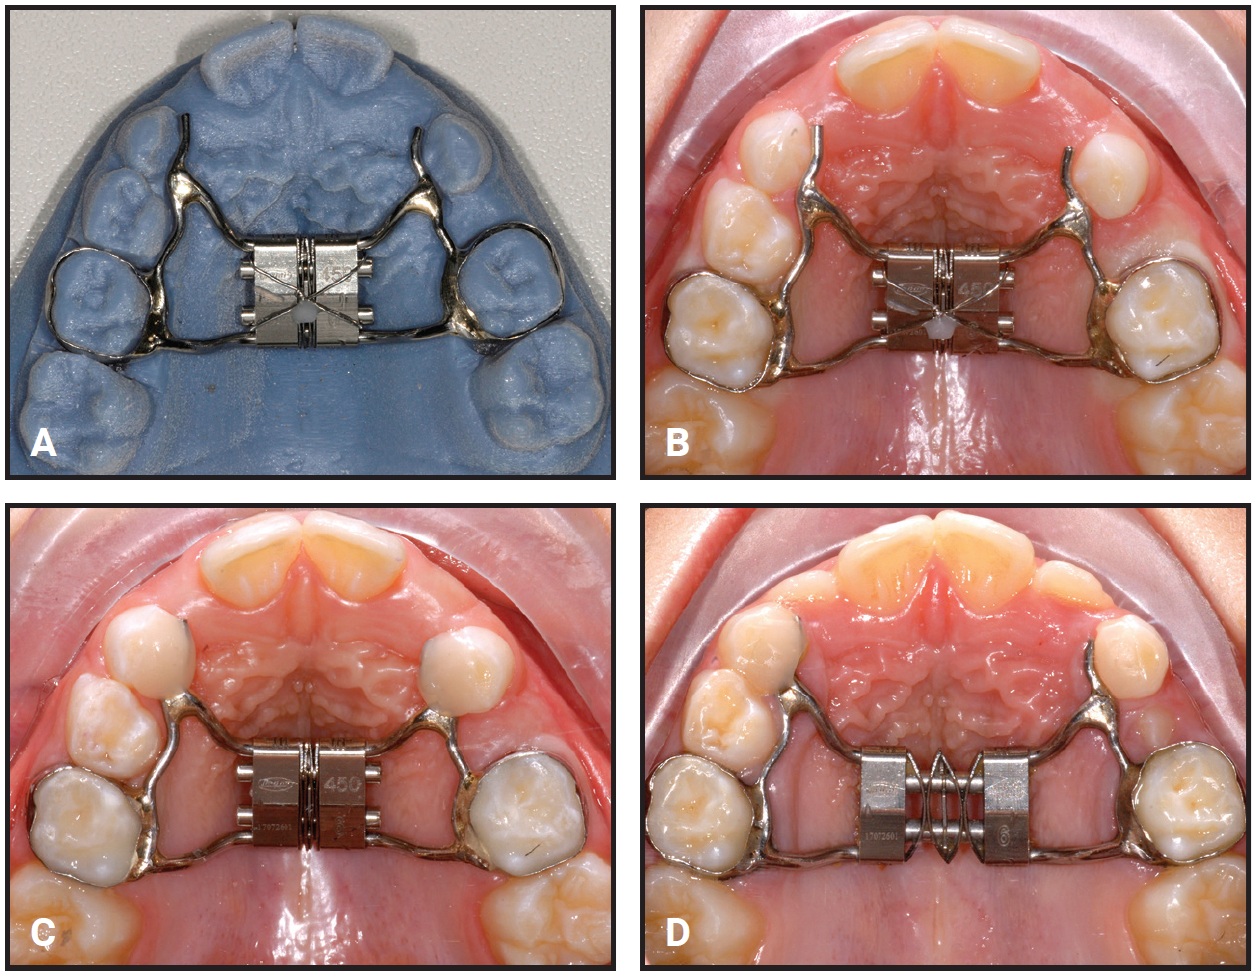

The design of the Self Expander is similar to that of a Leaf Expander,16 except that it is equipped with three preactivated, nickel titanium double springs instead of a leaf spring and a reactivation screw (Fig. 1). These leaf springs, which are compressed during fabrication in the laboratory, recover their shape during deactivation, generating a constant 450g of force for as much as 9mm of calibrated expansion.

Fig. 1 A. Self Expander* with three double-leaf springs compressed by laboratory before delivery. B. Springs decompress during treatment and generate constant 450g of force.

Like the Leaf Expander, the Self Expander is typically anchored to the deciduous teeth,17,18 with the upper first permanent molars left free to expand spontaneously (Fig. 2). The body of the 11mm × 12mm × 4mm screw can be adapted to fit a narrow palate or an arch with transverse deficiency. The arms connecting the screw and the lateral components must be kept about 2.5mm clear of the palatal mucosa to avoid ulceration. The screw is blocked with metal ligatures that are removed immediately after cementation to start the self-expansion.

Fig. 2 A. Self Expander on prototype model created from stereolithographic (STL) file of intraoral scan. B. Expander in mouth, with metal ligature still blocking compressed expansion leaves. C. Ligature wire removed immediately after banding. D. Appliance during active expansion.